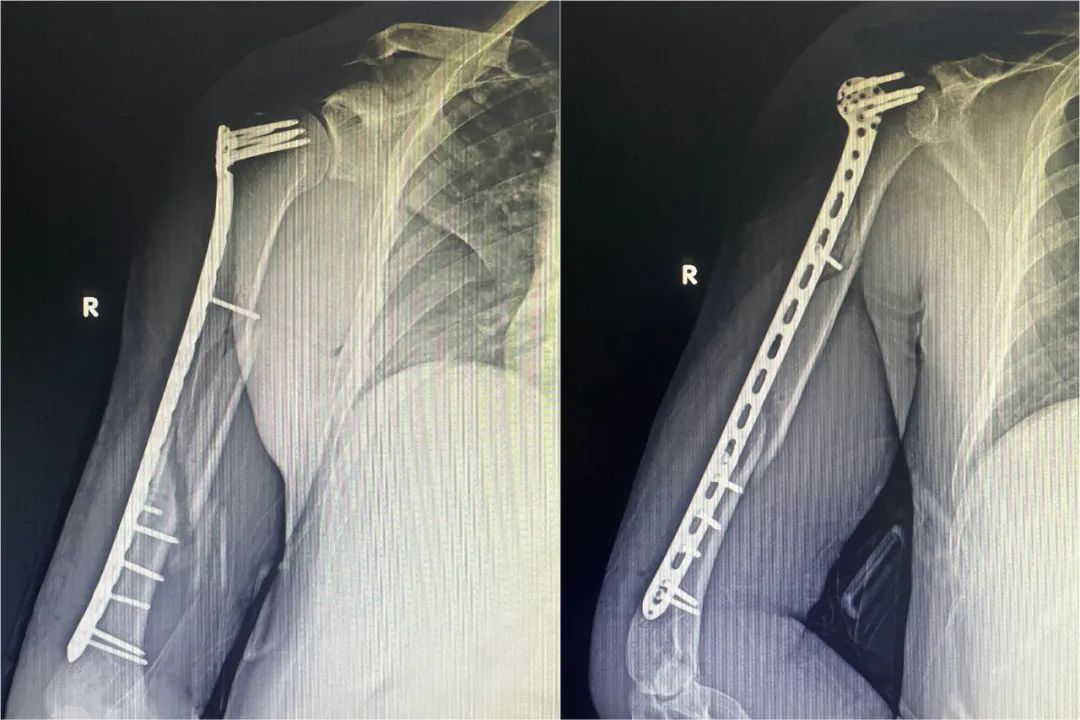

钢板固定